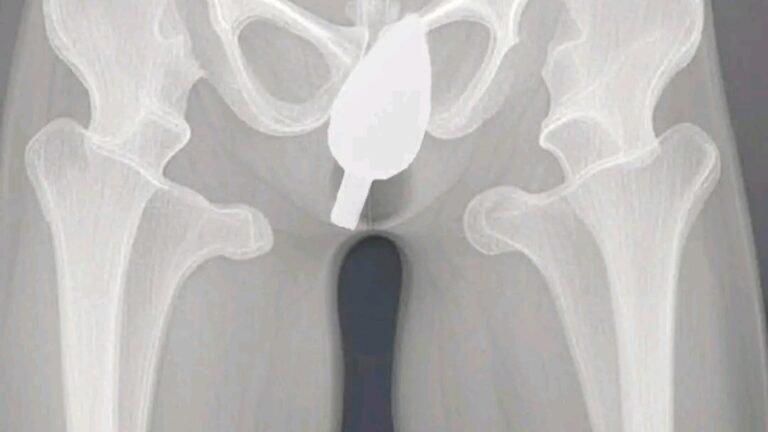

He got stuck while he was…